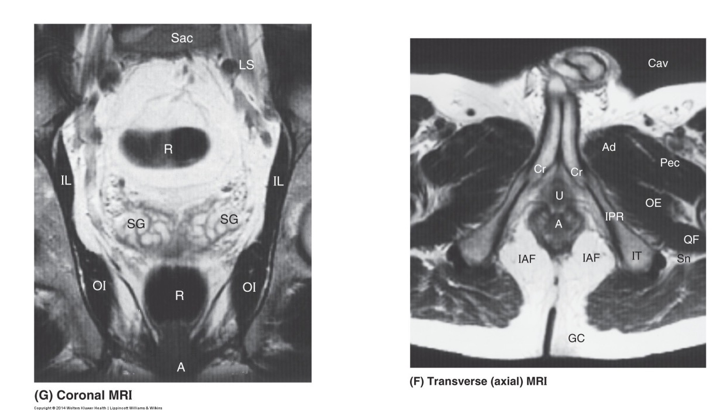

• The median view shows the relationship between the pubic symphysis (Sy), urinary bladder (UB), prostate gland (P), seminal vesicle (SG) and rectum (R).

The coronal image shows the bladder sitting immediately superior to the prostate gland. Immediately inferior to the prostate gland is the pelvic floor and then the bulb of the penis (B).

• The coronal MRI shows the highly coiled nature of the inside of the seminal vesicles (SG). At this coronal sectional level through the body, the structure posterior to the seminal vesicles can be seen appearing above and below the seminal vesicles – the rectum (R).

The transverse MRI image shows the crura (Cr) – erectile tissues that form the corpora cavernosa of the penis and the urethra (U) in the bulb of the penis. Posterior to this is the anal canal (A). Either side of the anal canal is a fat-filled space called the ischioanal fossa (IAF) part of the anal triangle.